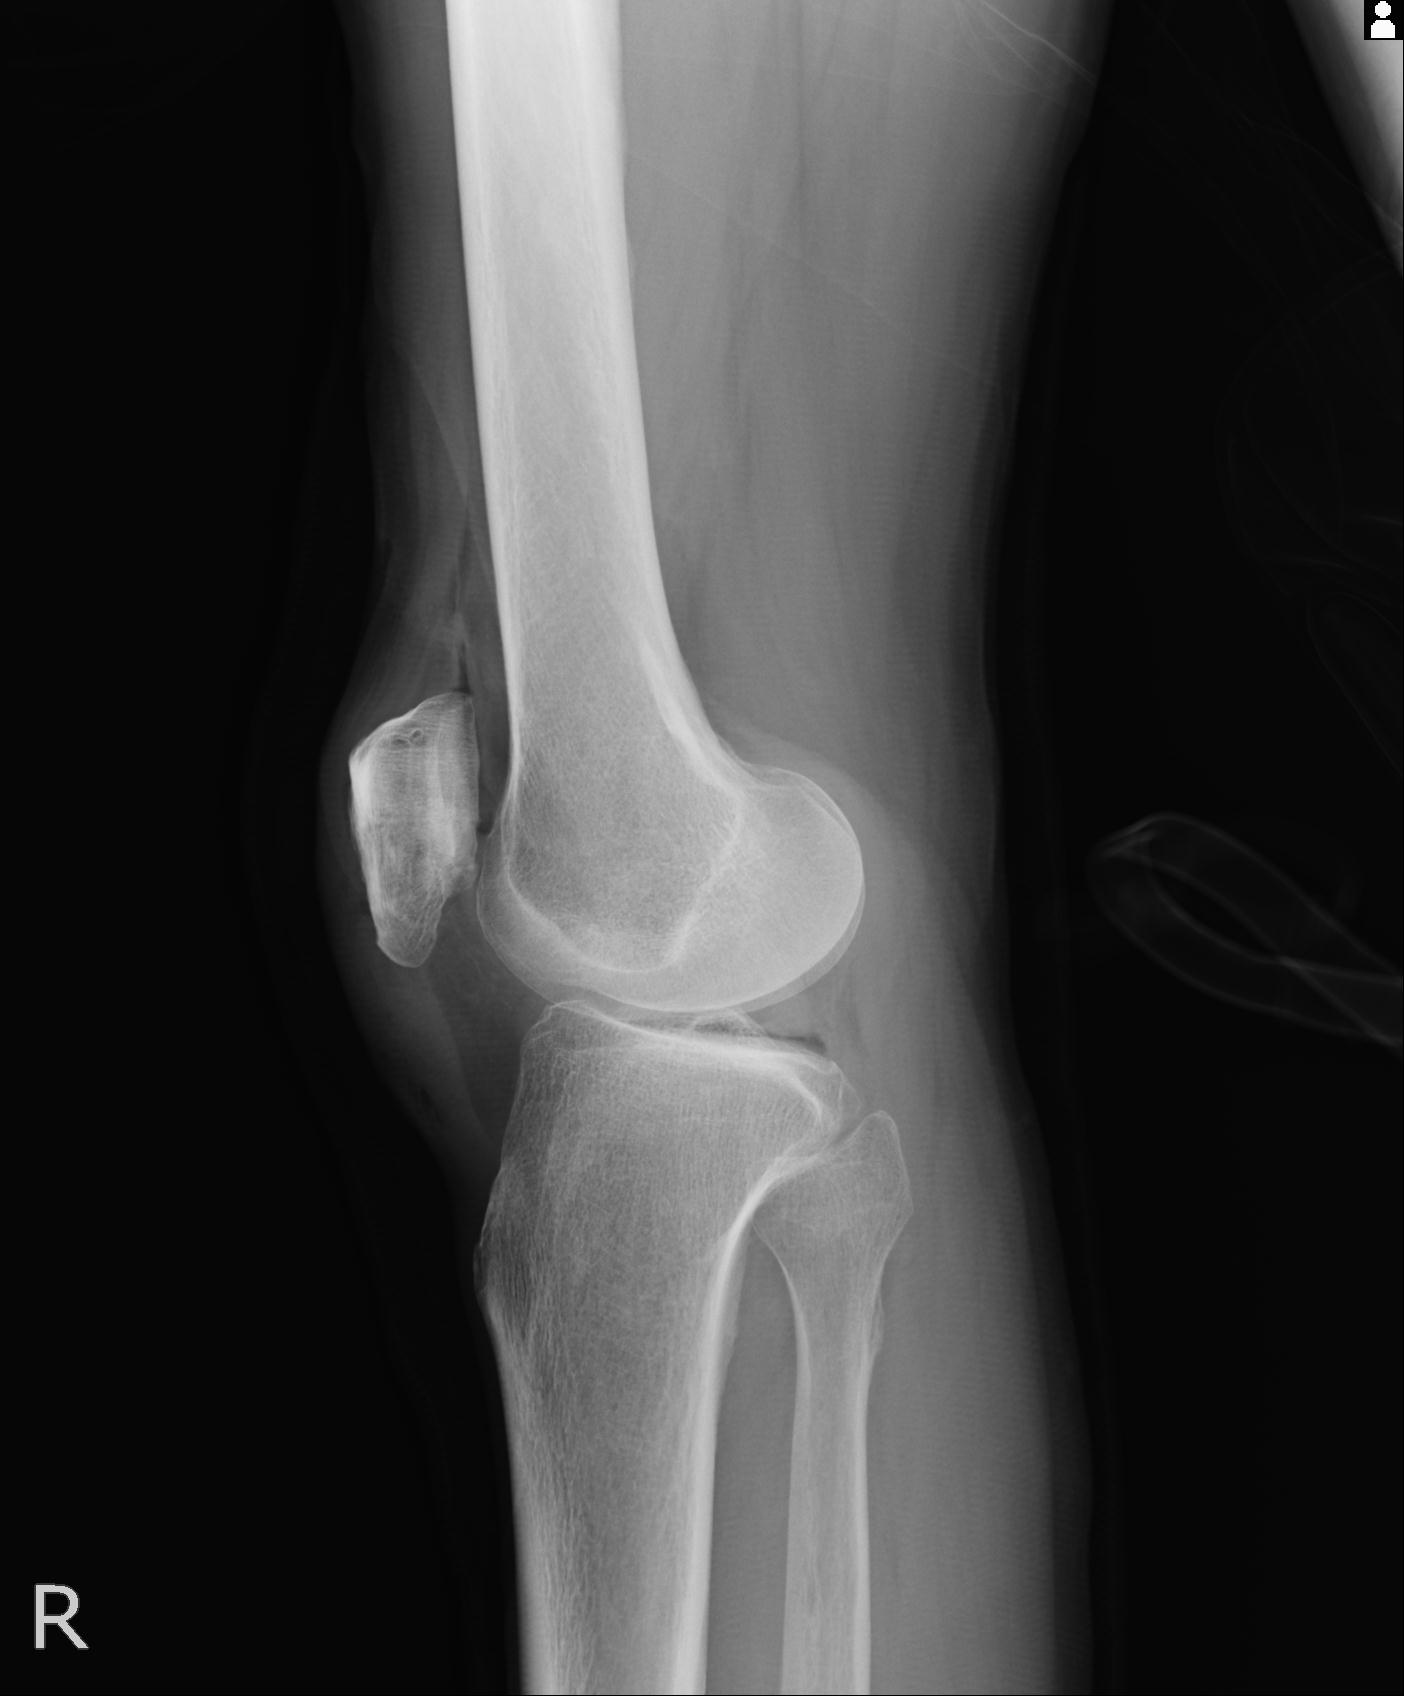

49554 3/13 膝 4R 3/16 4R 1/18 2R 78歳男性 膝蓋骨骨折